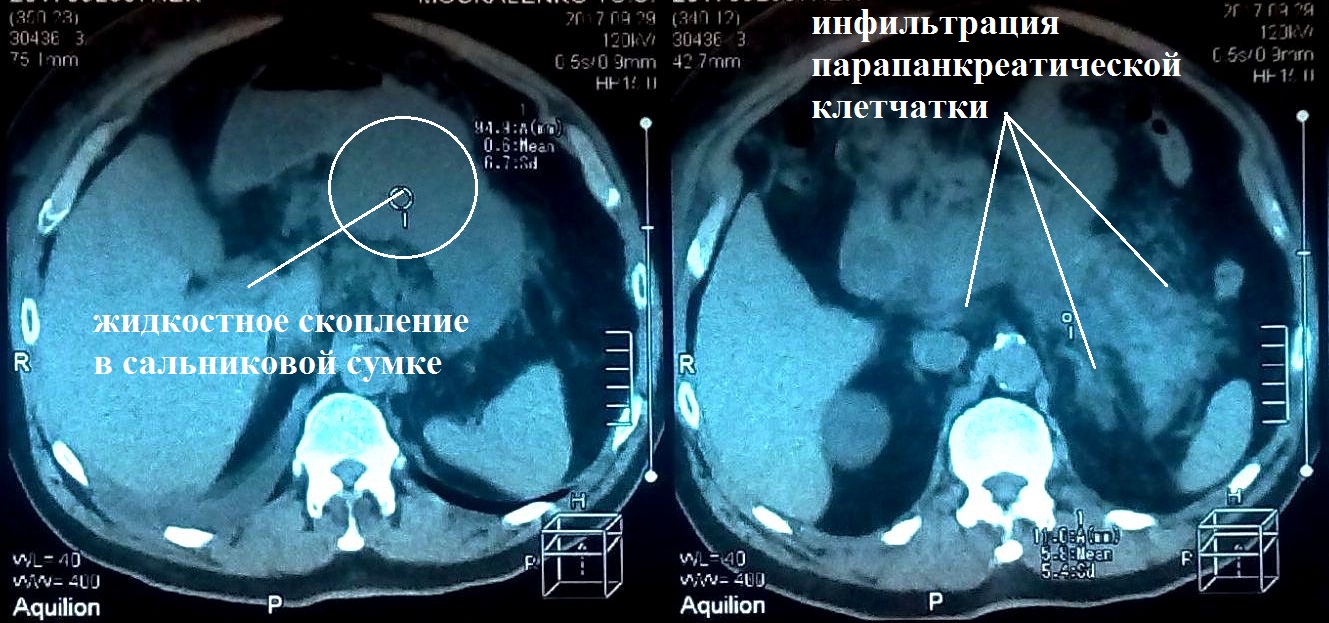

Пациент М., 69 лет, поступил в клинику 21.09.2017 г. на первые сутки от начала заболевания. При клинико-инструментальном обследовании установлен предварительный диагноз: острый тяжелый панкреатит, оментобурсит (рис. 1).

Рис. 1. КТ брюшной полости больного М. от 21.09.2017 г. (1-е сут болезни)

Начато консервативное лечение согласно клиническим рекомендациям. В ходе динамического инструментального (УЗИ, КТ) контроля на 8-е сут выявлено формирование острого жидкостного скопления (ОЖС) в сальниковой сумке (рис. 2). На 13-е сут заболевания, 04.10.2017 г., появились признаки инфицирования ОЖС — повышение температуры тела до 38,5 °С, лейкоцитоз до 11,3 × 109/л, С-реактивный белок — 156 мг/л, что явилось показанием к оперативному вмешательству.

Рис. 2. КТ брюшной полости больного М. от 29.09.2017 г. (8-е сут болезни)

С 18.10.2017 г. (27-е сут болезни) больной стал предъявлять жалобы на повышение температуры тела до 38–38,5 °C в вечерние часы. В анализах крови отмечено увеличение числа лейкоцитов до 12,3 × 109/л, уровня С-реактивного белка до 224,3 мг/л. При КТ живота от 19.10.2017 г. выявлено формирование жидкостного образования в корне брыжейки тонкой кишки, поперечной ободочной кишки, отграниченного тонкой капсулой неправильной формы размерами до 4,0 × 7,5 × 4,5 см с неоднородным содержимым (рис. 6).

Рис. 6. Абсцесс забрюшинного пространства в области корня брыжейки тонкой кишки. КТ брюшной полости больного М. от 19.10.2018 г. (28-е сут болезни)